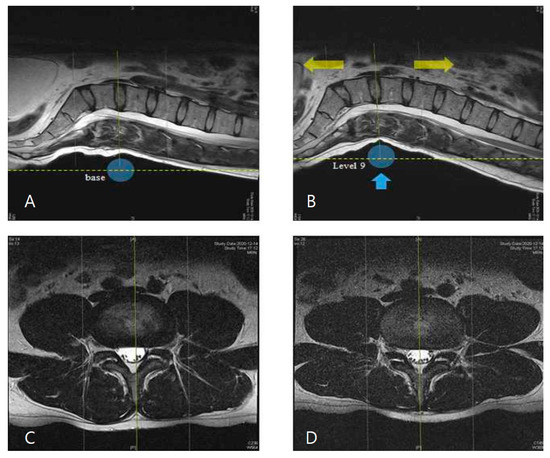

2.3. Measurements of Intervertebral Height and Lumbar Cobb’s Angle under Traction Mode

2.4. Morphological Observation of Spinal Structures in Axial View of L4–5 Disc

3.3. Observation of MR Images of the Central Spinal Canal Area